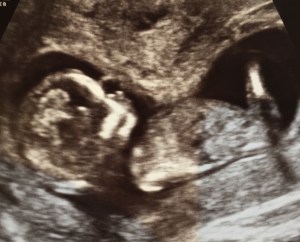

My dating scan was between christmas and new year and showed me just a few days further along than expected and even though this is my 7th baby I am always in awe of the fact that after such a short time of developing there is a fully formed baby inside! The scan was particularly clear, we could count fingers and toes (seriously, the baby was only 7cm long at this point, how tiny were those little toes!) and see it swallowing, waving and moving around. Even though I have done this a few times already I am so fascinated and amazed.